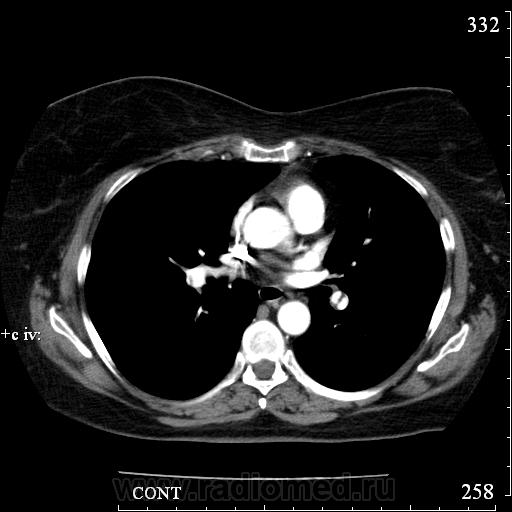

Коллега Mitkamfer спрашивал: "Может из наших коллег еще кто свои наблюдения покажет". Представляю случай ТЭЛА у женщины 57 лет с тромбозом подвздошной вены и распространением тромба в нижнюю полую вену.

Клиники особой не было, исследование делали с целью, а нет ли у нее еще и ТЭЛА. При КТ-ангиографии признаки пристеночных тромбов в правой и левой легочной артериях и единичных мелких пристеночных тромбов в мелких ветвях нижнедолевых артерий с обеих сторон, организовавшихся (лентовидных) тромбов в левой легочной артерии. При этом диаметры легочного ствола, правой и левой ЛА не расширены. Как видите, они такие разные, эти ТЭЛА

Изменения в легких при этом весьма скромные: в правом легком особых изменений нет, в левом - признаки организовавшегося инфаркта легкого - радиальные фиброзные тяжи в базально-латеральном сегменте нижней доли левого легкого.

Рисунок 32. Дополнительные КТ-ангиографические признаки ТЭЛА у больной 58 лет.